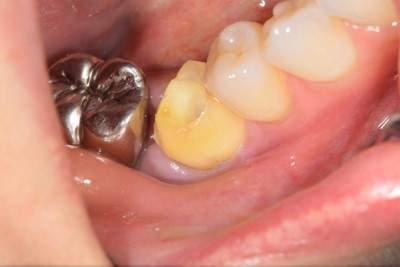

2022.2.5 抜歯後の消毒

口腔内写真

CT画像

骨の状態はそこまで悪くないが、欠損が大きい。

2022.3.12 抜歯1ヶ月後・移植

移植オペ

抜歯をして1ヶ月後、歯ぐきが治ってから、移植をおこなった。

移植時は動揺が大きいため、隣の歯にワイヤーで固定した。